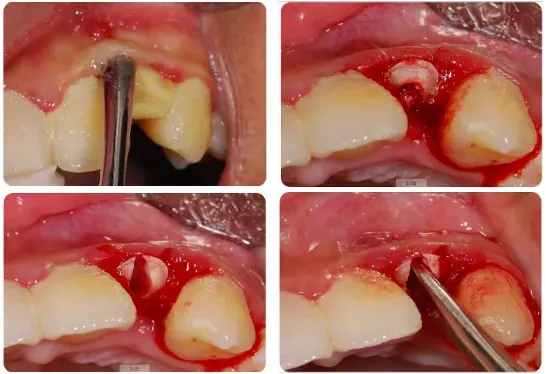

2、拔牙器械的微创拔牙技巧;

牙钳拔牙的微创使用技巧

●“八字旋转法”微创拔牙技巧

●怎样选择合适的微创牙挺

●你是否真的会使用牙挺

●牙钳牙挺的联合使用技巧